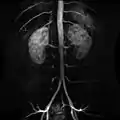

Contrast enhanced MRA of the abdominal aorta demonstrating normal paired arteries.